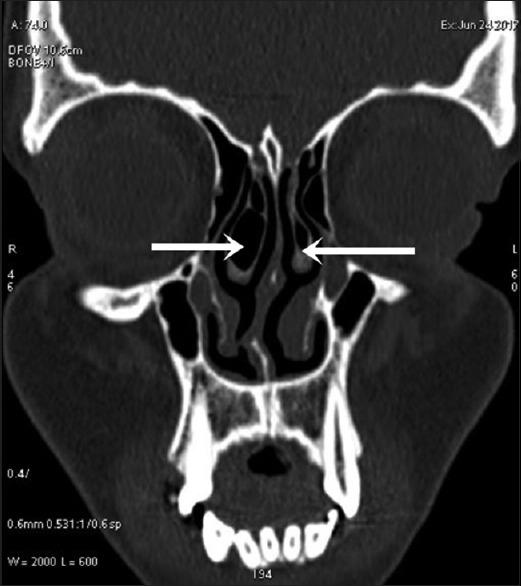

Among 250 study population, 100 were females and 150 males. Among these 423 cases of anatomical variants were observed. The most common anatomical variants were pneumatization of the middle nasal turbinates 30.73%. This is followed by agger nasi cells 21.64%, Haller's cells 22.91%, septal deviation 21.91%, and sphenoid sinus septation (20.18%).

CT is the gold standard in the radiologic investigation of the paranasal sinuses, sinonasal lesions, and inflammatory disease or pre- and post-surgical assessment. It has the capability of disclosing in greatest detail any anatomical variations, which could be causing or precipitating the sinusitis.